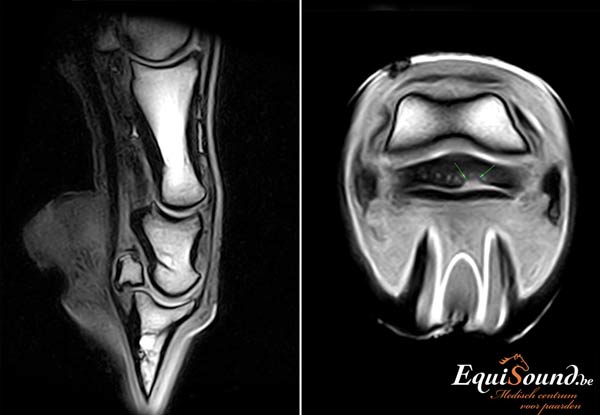

EquiSound beschikt over het eerste MRI-toestel in de Benelux dat het paard kan scannen van ondervoet tot de achterknie, inclusief het hoofd en de nek. Het is ook de eerste MRI-scanner ter wereld die een paard zowel rechtopstaand als liggend in beeld kan brengen. Geen enkel onderdeeltje van het paard, van ledematen tot hoofd, ontsnapt nog aan het oog van onze dierenartsen.

Een MRI-scanner is een geavanceerd toestel dat ons in staat stelt zowel de weke delen (ligamenten, pezen en kraakbeen) als het beenderstel van een paard in 3 dimensies te evalueren (3D). Dit is niet mogelijk met radiografie en echografie. Bovendien levert de technologie veel gedetailleerdere beelden af dan radiologie, echografie of CT. De interpretatie van de MRI-beelden wordt bij EquiSound ondersteund door ervaren MRI-specialisten Myra Barrett en Kurt Selberg vanuit de USA . Op die manier verzekert EquiSound topdiagnostiek bij uw paard vanaf het eerste uur.

Het hoogtechnologische toestel van EquiSound kan een paard zowel in een rechtstaande als liggende positie scannen. De ondervoet onderzoeken we bijvoorbeeld terwijl het paard recht blijft staan. Om bijvoorbeeld de achterknie te scannen, brengen we het paard dan weer even onder narcose (algemene anesthesie). Dit is noodzakelijk omdat het paard anders te veel beweegt. Elke opname neemt immers 3 tot 6 minuten in beslag. Van paarden onder algemene anesthesie kunnen we bovendien beelden maken met een hogere resolutie. Zo kan de prognose voor uw paard nog beter ingeschat worden. Een geassisteerde recovery zorgt ervoor dat het paard veilig ontwaakt.